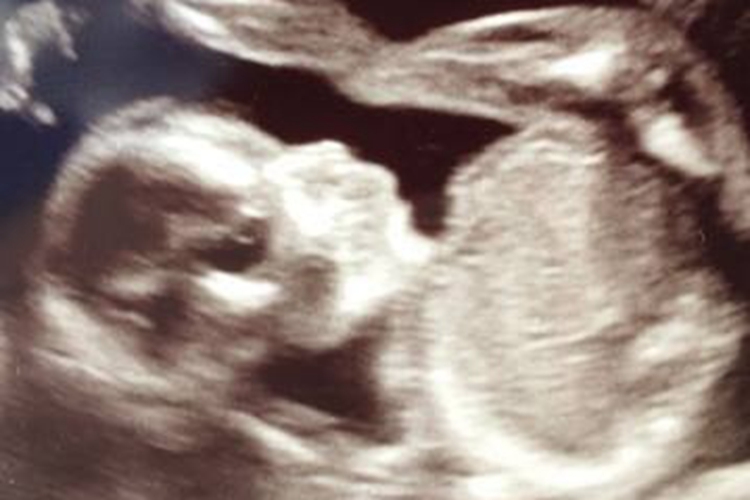

孕11周属于孕早期,B超可以清晰显示胎儿的形态,颜面部形成,手指、足趾明显,胎儿四肢可活动,身长在61-87毫米。此时进行B超检查的主要目的是确定宫内妊娠,排除异位妊娠、滋养细胞疾病、盆腔肿块等。通过B超也可以测量胎儿头臀长度,从而能较准确地估计孕周,校正预产期。